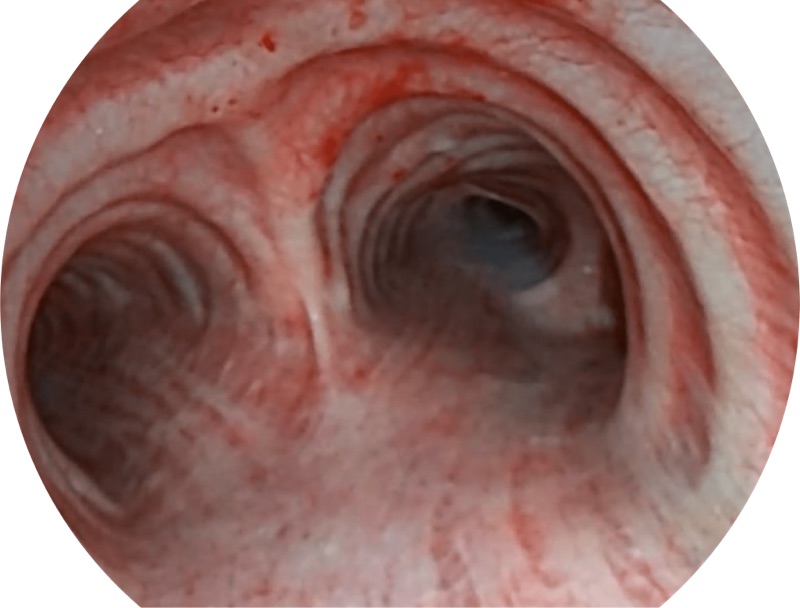

白光

帮助医生更加清晰地观察气管表面病灶